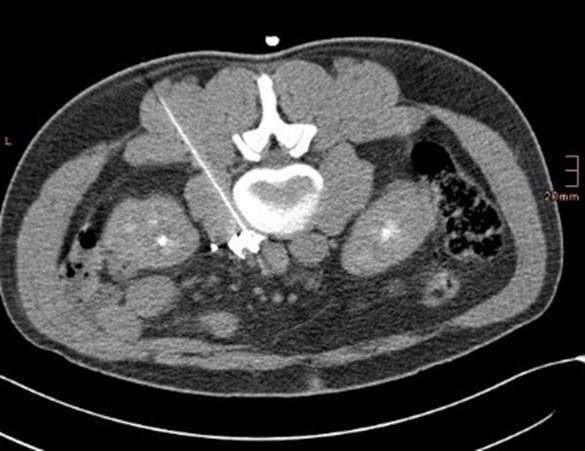

Tumorablationen (RITA, RFA, MWA)

Wir führen minimal-invasive Thermoablationen von Lebertumoren, z.B. bei Leberkrebs oder Lebermetastasen, und von Nierentumoren durch. Auch Lungentumore und Knochentumore sind behandelbar. Wir verwenden Radiofrequenz- oder Mikrowellen-Technik. Die Mikrowellenantenne in Form einer Nadel wird CT-gezielt während einer Kurznarkose zum Tumor vorgeführt. Über diese Sonde wird die Tumorregion erhitzt und der Tumor verkocht. Bei unkompliziertem Verlauf wird die Patientin oder der Patient über Nacht stationär überwacht und dann nach Hause entlassen.